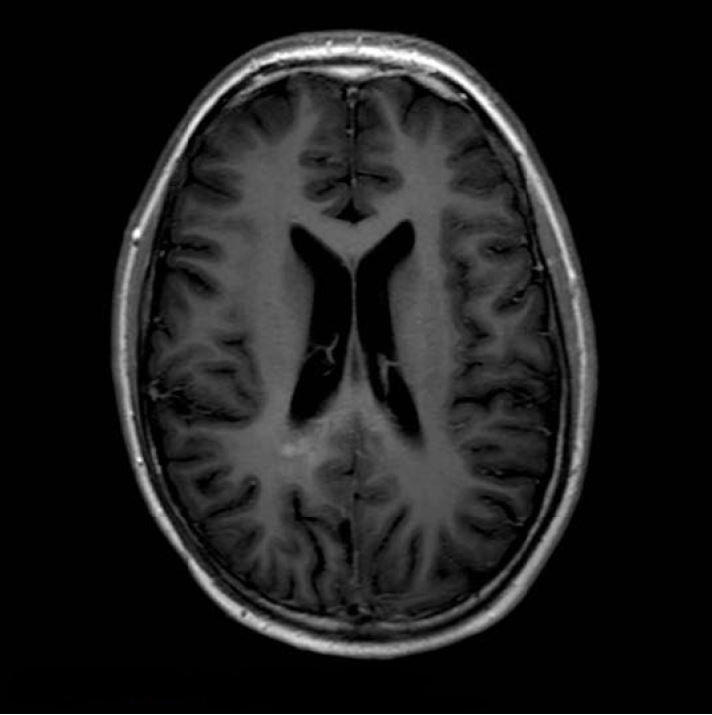

На T2 зона гіперсигналу була видна в передньо-нижній зоні від резекційної порожнини з нечітким контрастним посиленням, а також на мозолистому тілі, яке чітко збільшене порівняно з зображеннями FU МРТ за 1 місяць до (рис. 5 і 6). Це ураження показало обмеження дифузії (рис. 8).

Рисунок 5 T2WI, серпень 2011